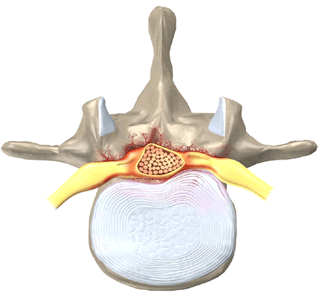

- Характерный вид ЗПС в виде «перевернутой буквы Т» или «галстука-бабочки» на аксиальных срезах.

- Характерный вид ЗПС а виде «перевернутой буквы Т» или «галстука бабочки» на аксиальных изображениях.

Сужение позвоночного канала в переднезаднем направлении может быть обусловлено его вторичным стенозом, гипертрофией задней продольной и жёлтой связки, спондилолистезом. Для установления стеноза позвоночного канала необходимо измерение канала в сагиттальной плоскости. Абсолютным стенозом принято считать уменьшение диаметра канала до 10 мм и менее. Величина в 10-15 мм соответствует частичному стенозу. Толщина задней продольной связки в норме не должна превышать 2 мм, желтой связки — 3 мм.